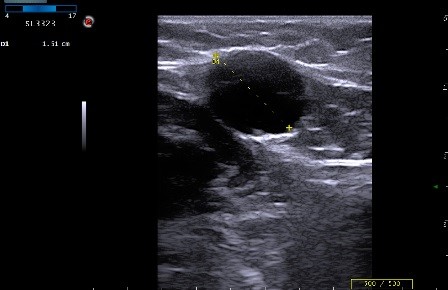

Изменение окраски кожных покровов конечности является одним из основных симптомов острого илиофеморального тромбоза. Именно этот метод стал «золотым стандартом» в обследовании больных с тромбофлебитом нижних конечностей, и именно благодаря ему врач может более четко определять тактику дальнейшего лечения и наблюдения больного. Информация на сайте предоставлена исключительно в ознакомительных целях и не является руководством к действию.